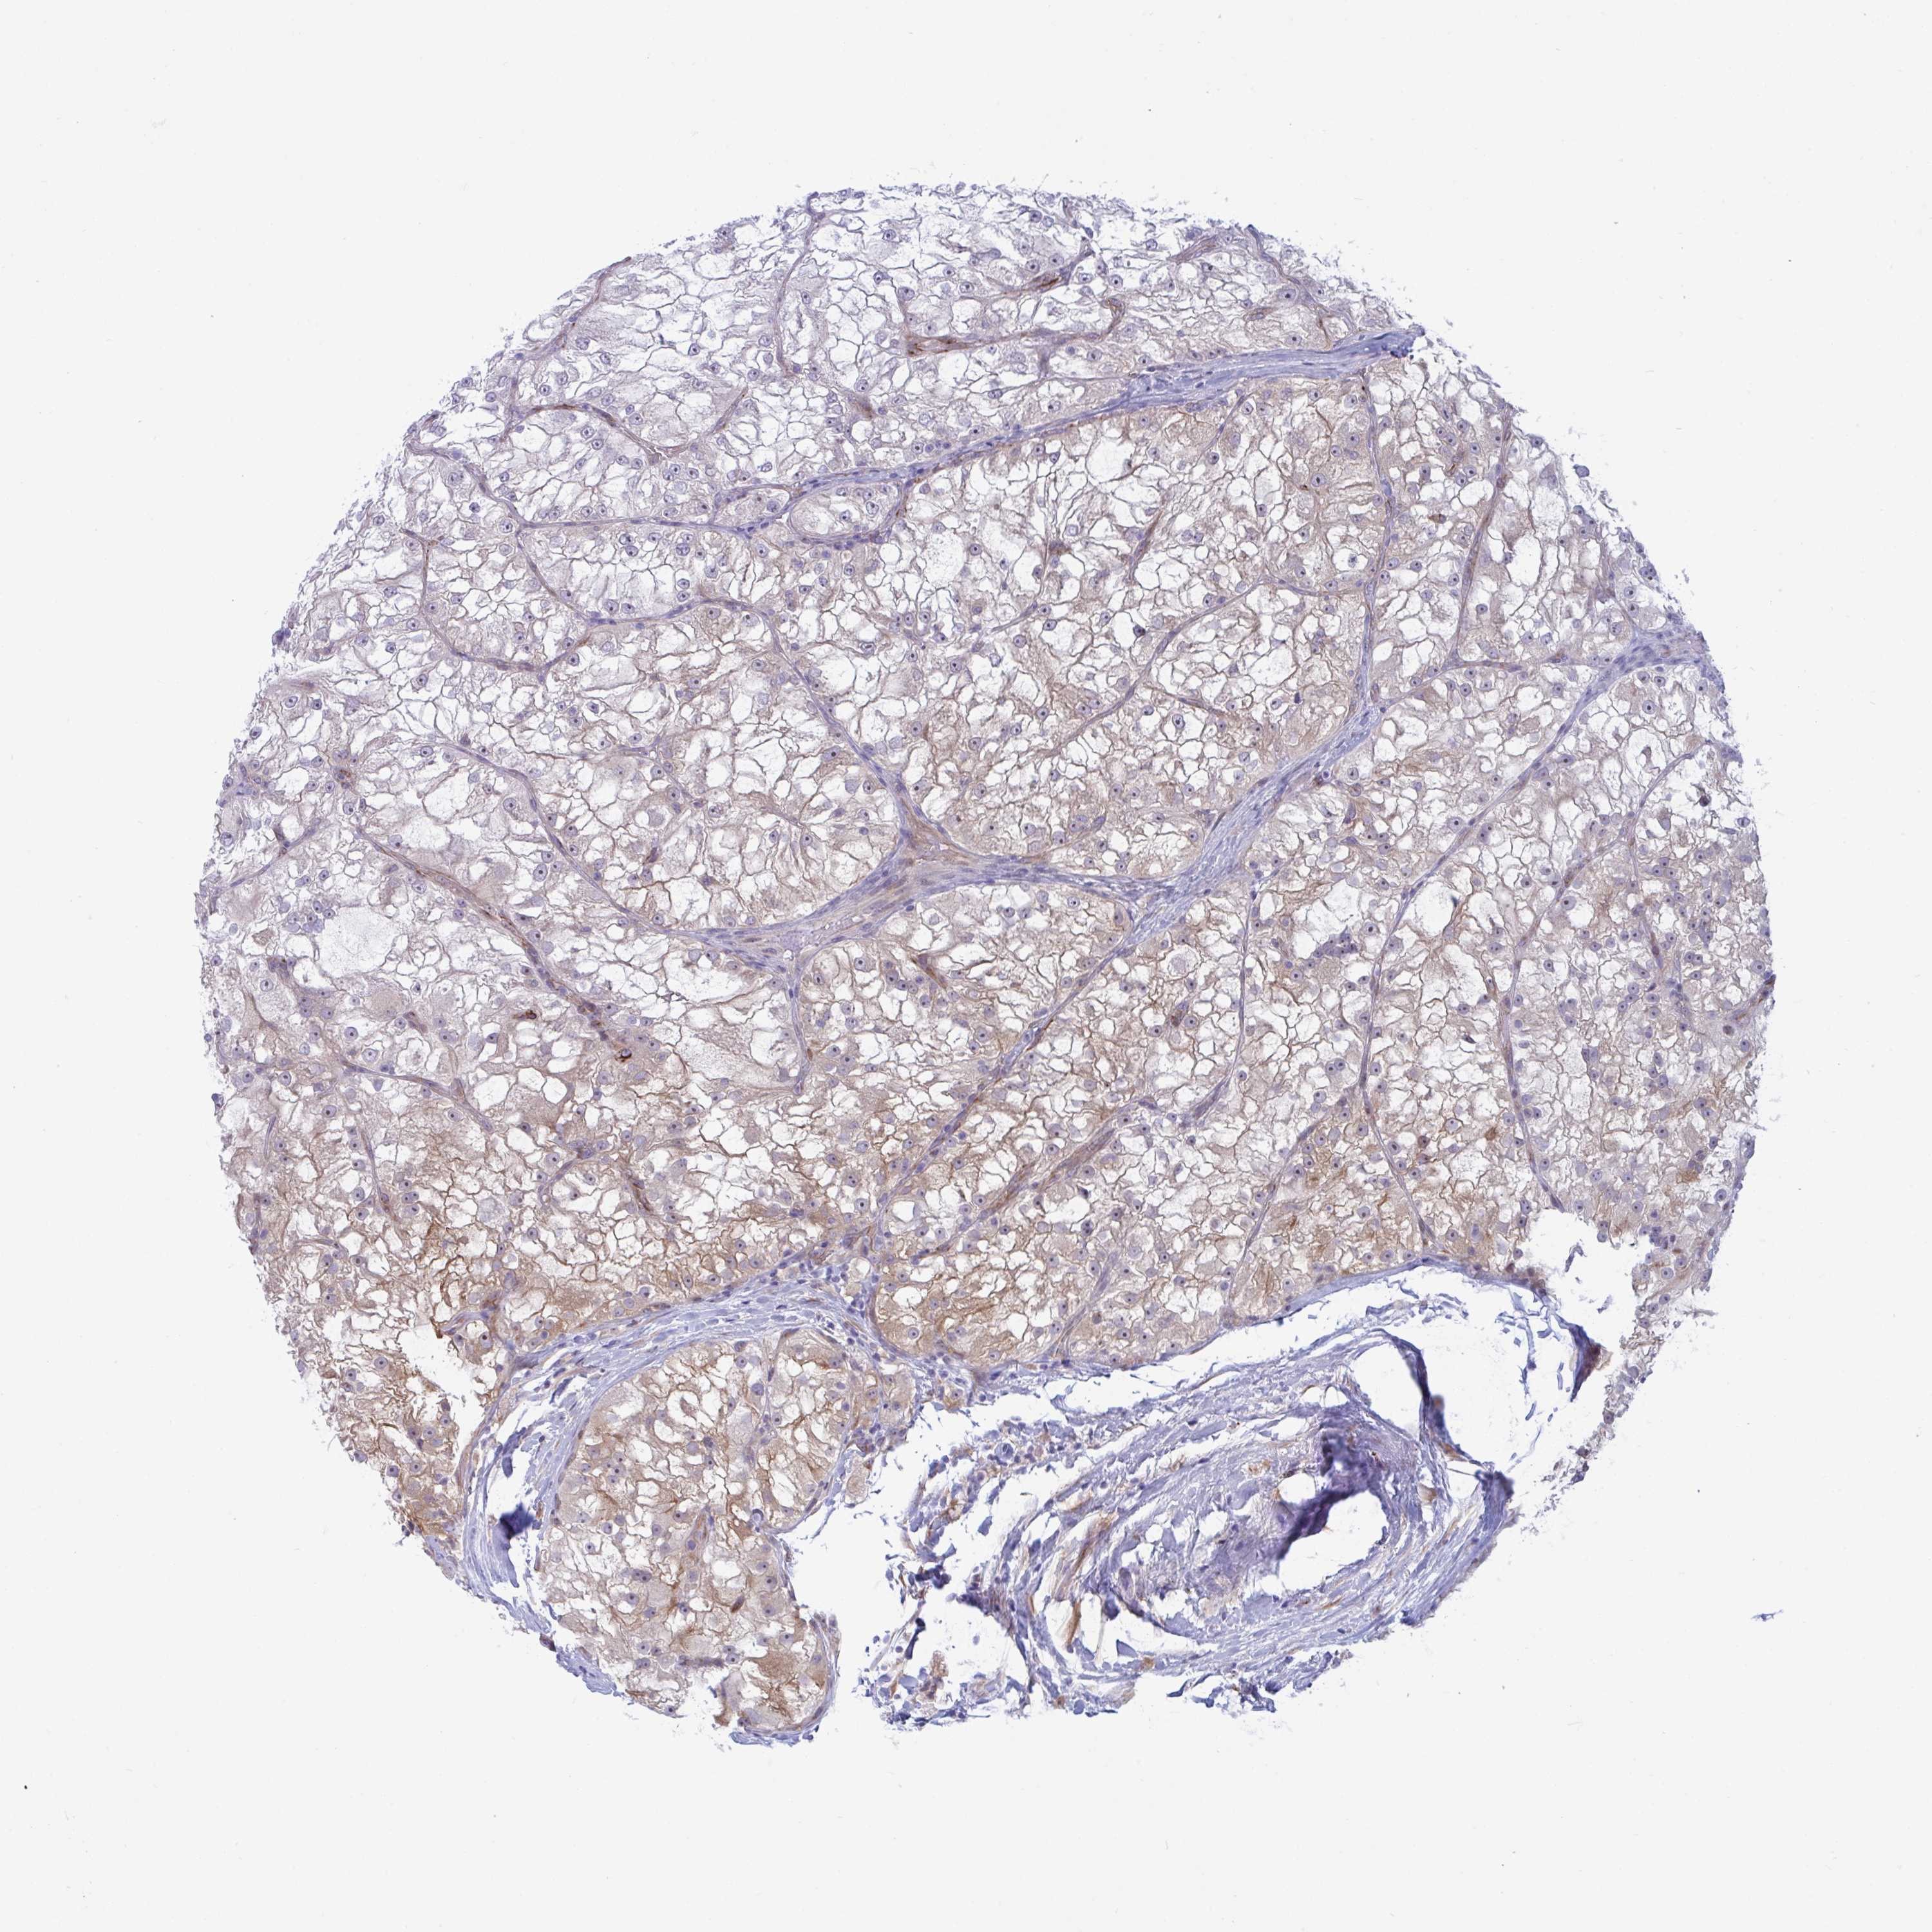

KIDNEY RENAL CLEAR CELL CARCINOMA (VALIDATION) - Interactive survival scatter ploti

The Survival Scatter plot shows the clinical status (i.e. dead or alive) for all individuals in the patient cohort, based on the same data that underlies the corresponding Kaplan-Meier plots. Patients that are alive at last time for follow-up are shown in blue and patients who have died during the study are shown in red.

The x-axis shows the expression levels (FPKM) of the investigated gene in the tumor tissue at the time of diagnosis. The y-axis shows the follow-up time after diagnosis (years). Both axes are complimented with kernel density curves demonstrating the data density over the axes. The top density plot shows the expression levels (FPKM) distribution among dead (red) and alive patients (blue). The right density plot shows the data density of the survived years of dead patients with high and low expression levels respectively, stratified using the cutoff indicated by the vertical dashed line through the Survival Scatter plot. This cutoff is automatically defined based on the FPKM cutoff that minimizes the p-score. The cutoff can be changed by dragging the vertical line or by entering a cutoff value in the square labeled "Current cut-off".

Under the Survival Scatter plot the p-score landscape (black curve; left axis) is shown together with dead median separation (red curve; right axis). Dead median separation is the difference in median mRNA expression between patients who have died with high and low expression, respectively. It is calculated as follows: median FPKM expression of dead patients with high expression - median FPKM expression of dead patients with low expression. This is intended to aid the user in visually exploring custom cutoffs and the associated p-scores and dead median separation.

Individual patient data is displayed and can be filtered by clicking on one or more of the category buttons on the top of the page. Categories describing expression level and patient information include: high, low, alive, dead, female, male and tumor stages. The scale of the x-axis can be toggled between linear and log-scale by clicking on the "x log" button. Mouse-over function shows TCGA ID, patient information and mRNA expression (FPKM) for each patient.

& Survival analysisi

Kaplan-Meier plots summarize results from analysis of correlation between mRNA expression level and patient survival. Patients were divided based on level of expression into one of the two groups "low" (under cut off) or "high" (over cut off). X-axis shows time for survival (years) and y-axis shows the probability of survival, where 1.0 corresponds to 100 percent.

PRRT4 is not prognostic in Kidney Renal Clear Cell Carcinoma (validation)

TCGA RNA samplesi

RNA-seq data is reported as average FPKM (number Fragments Per Kilobase of exon per Million reads), generated by the The Cancer Genome Atlas (TCGA) .

Normal distribution across the dataset is visualized with box plots, shown as median and 25th and 75th percentiles. Points are displayed as outliers if they are above or below 1.5 times the interquartile range. FPKM values of the individual samples are presented next to the box plot.

Average pTPM 0.1

Number of samples 100